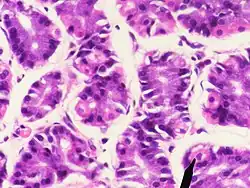

Parietal cells (also known as oxyntic cells) are epithelial cells in the stomach that secrete hydrochloric acid (HCl) and intrinsic factor. These cells are located in the gastric glands found in the lining of the fundus and body regions of the stomach.[1] They contain an extensive secretory network of canaliculi from which the HCl is secreted by active transport into the stomach. The enzyme hydrogen potassium ATPase (H+/K+ ATPase) is unique to the parietal cells and transports the H+ against a concentration gradient of about 3 million to 1, which is the steepest ion gradient formed in the human body. Parietal cells are primarily regulated via histamine, acetylcholine and gastrin signalling from both central and local modulators.